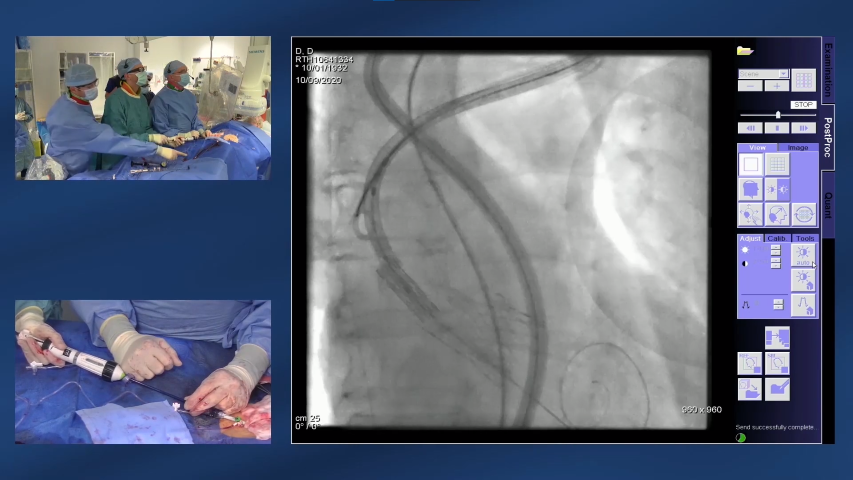

• The ViV TAVI procedure is similar to an initial TAVI intervention, with the failing valve used to guide the positioning of the replacement valve6

• The replacement valve is gradually deployed and the new bioprosthetic valve is placed tightly into the inside of the failed valve, pushing the old valve leaflets aside6

• Angiography is used to ensure accurate positioning of the valve6

Watch how a ViV procedure can be successfully completed. - 12 min